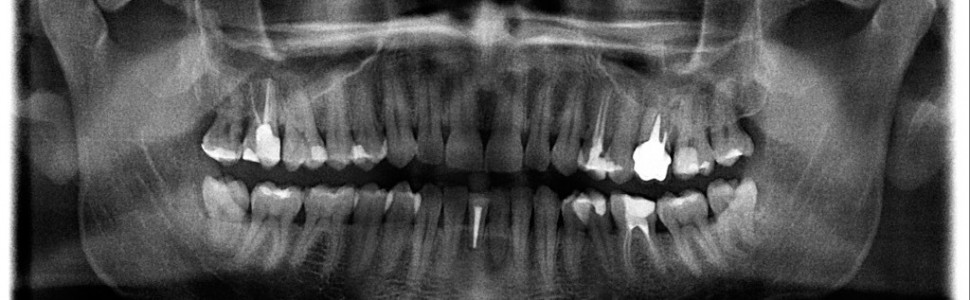

Radiologiczne obrazowanie systemu kanałów korzeniowych jest koniecznym elementem etapu diagnostyki, leczenia i kontroli pozabiegowej terapii endodontycznej. Stomatolodzy wykorzystują w endodoncji głównie wewnątrzustne zdjęcia zębowe. Celem pracy jest przedstawienie możliwości wykorzystania obrazowania rentgenowskiego w trakcie leczenia kanałowego.

Radiological imaging of root canal systems is an essential element at the stages of diagnosis, treatment and post-operative control in endodontic treatment. Dentists use mainly intraoral radiographs of teeth in endodontics. The aim of the study is to indicate the possibilities in using radiographic imaging during the course of endodontic treatment.